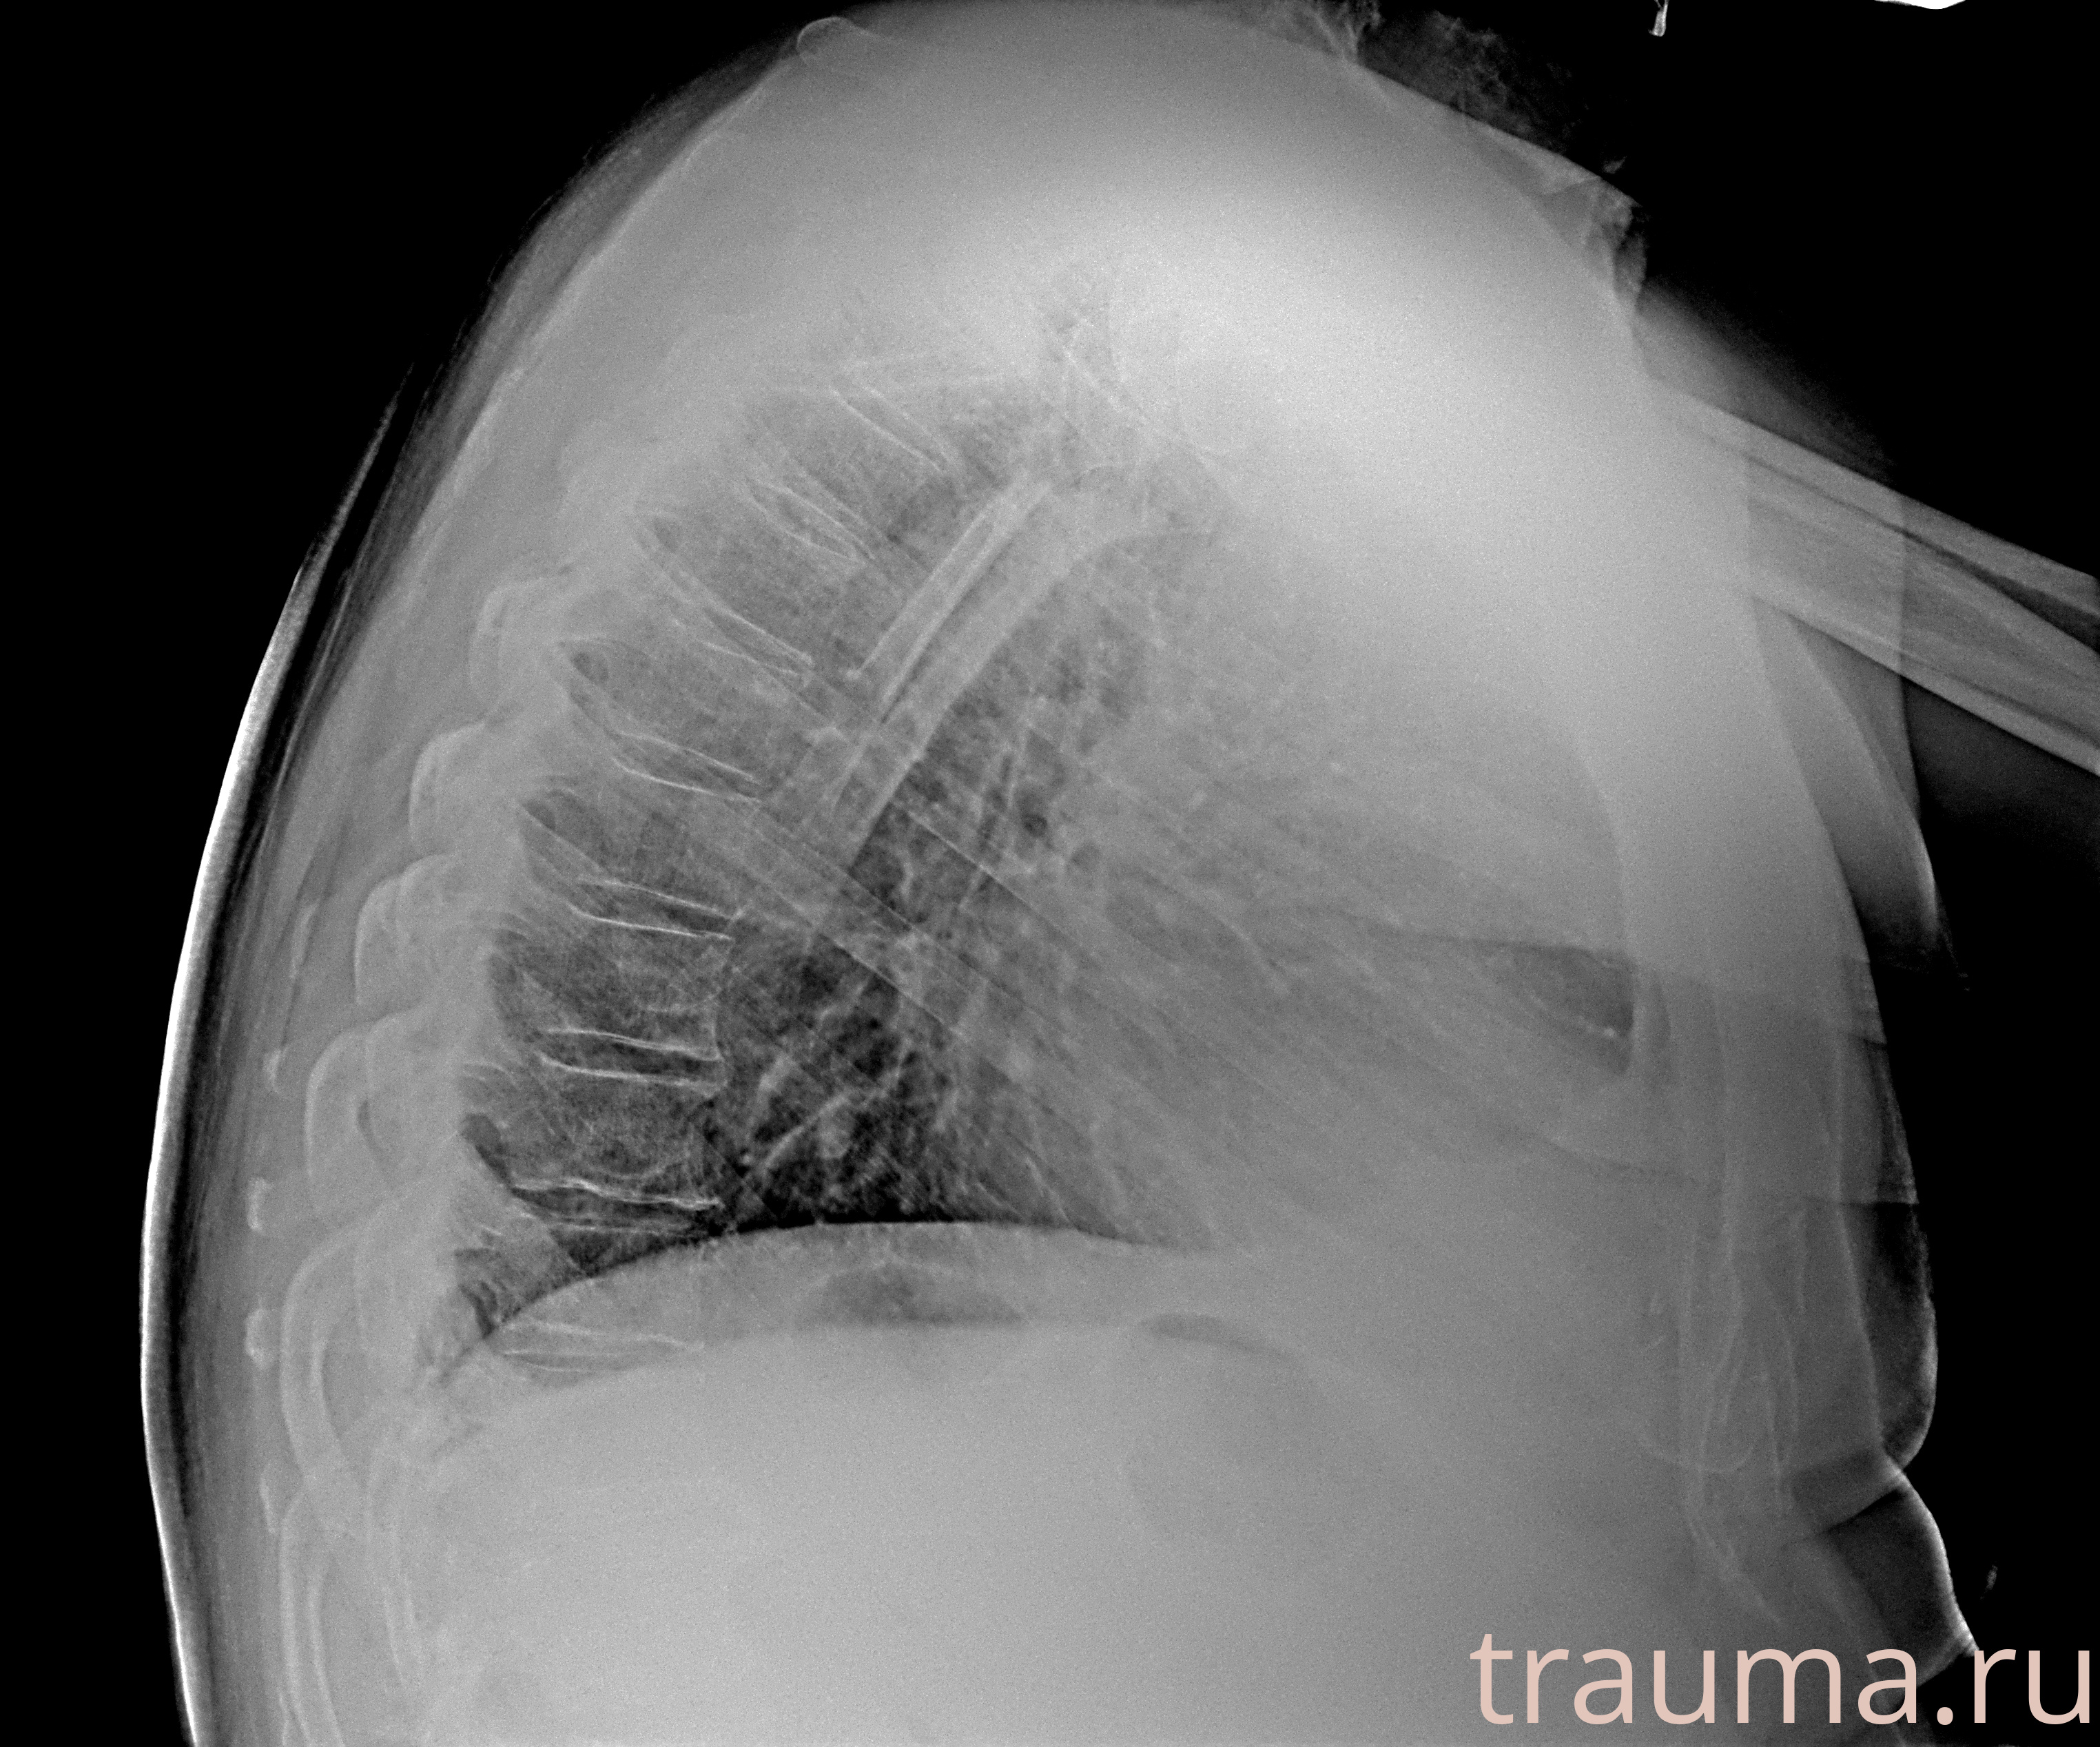

Рентген на дому: по вашему адресу приезжает врач-рентгенолог, травматолог-ортопед с мобильным рентгеновским аппаратом, проводит диагностику травмы или заболевания, делает необходимые рентгенограммы, дает рекомендации по дальнейшему лечению. Получить качественные снимки в домашних условиях возможно благодаря уникальной методике, разработанной МосРентген Центром для института  Склифосовского